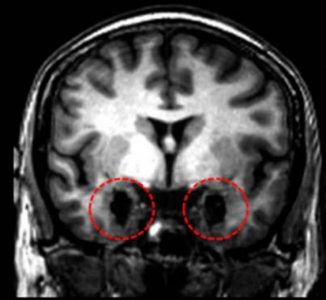

Patiente SM IRM Anatomique